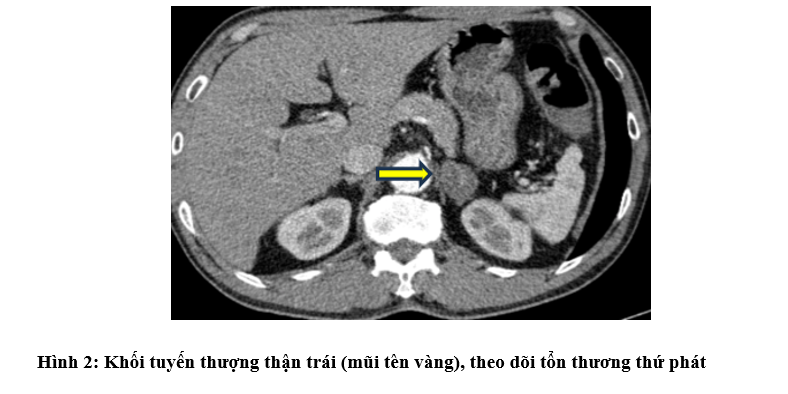

- Chụp Cắt lớp vi tính ổ bụng: Hình ảnh khối tuyến thượng thận trái 21x32mm - theo dõi tổn thương thứ phát. Đại tràng góc lách dày thành không đều quanh chu vi 15mm trên đoạn dài 61mm mất cấu trúc lớp, thâm nhiễm xung quanh kèm nhiều hạch lân cận lớn nhất kích thước 9x5mm

- Chụp PET/CT: Hình ảnh dày thành đại tràng góc lách, dày nhất 18mm, trên đoạn 41mm, tăng chuyển hóa, thâm nhiễm mỡ xung quanh. Vài hạch ở cạnh tổn thương đại tràng, cạnh động mạch chủ bụng và cạnh thân tụy tăng chuyển hóa, khả năng do di căn. Hình ảnh tổn thương bờ tua gai ở S3 phổi trái, kích thước 31x26x22mm, tăng chuyển hóa, khả năng là tổn thương ác tính nguyên phát. Hình ảnh vài hạch trung thất nhóm 5, 6, 7, hạch thượng đòn Phải tăng chuyển hóa, khả năng do di căn. Hình ảnh vài nốt bán đặc và kính mờ rải rác nhu mô phổi 2 bên, có nốt tăng chuyển hóa, khả năng do di căn